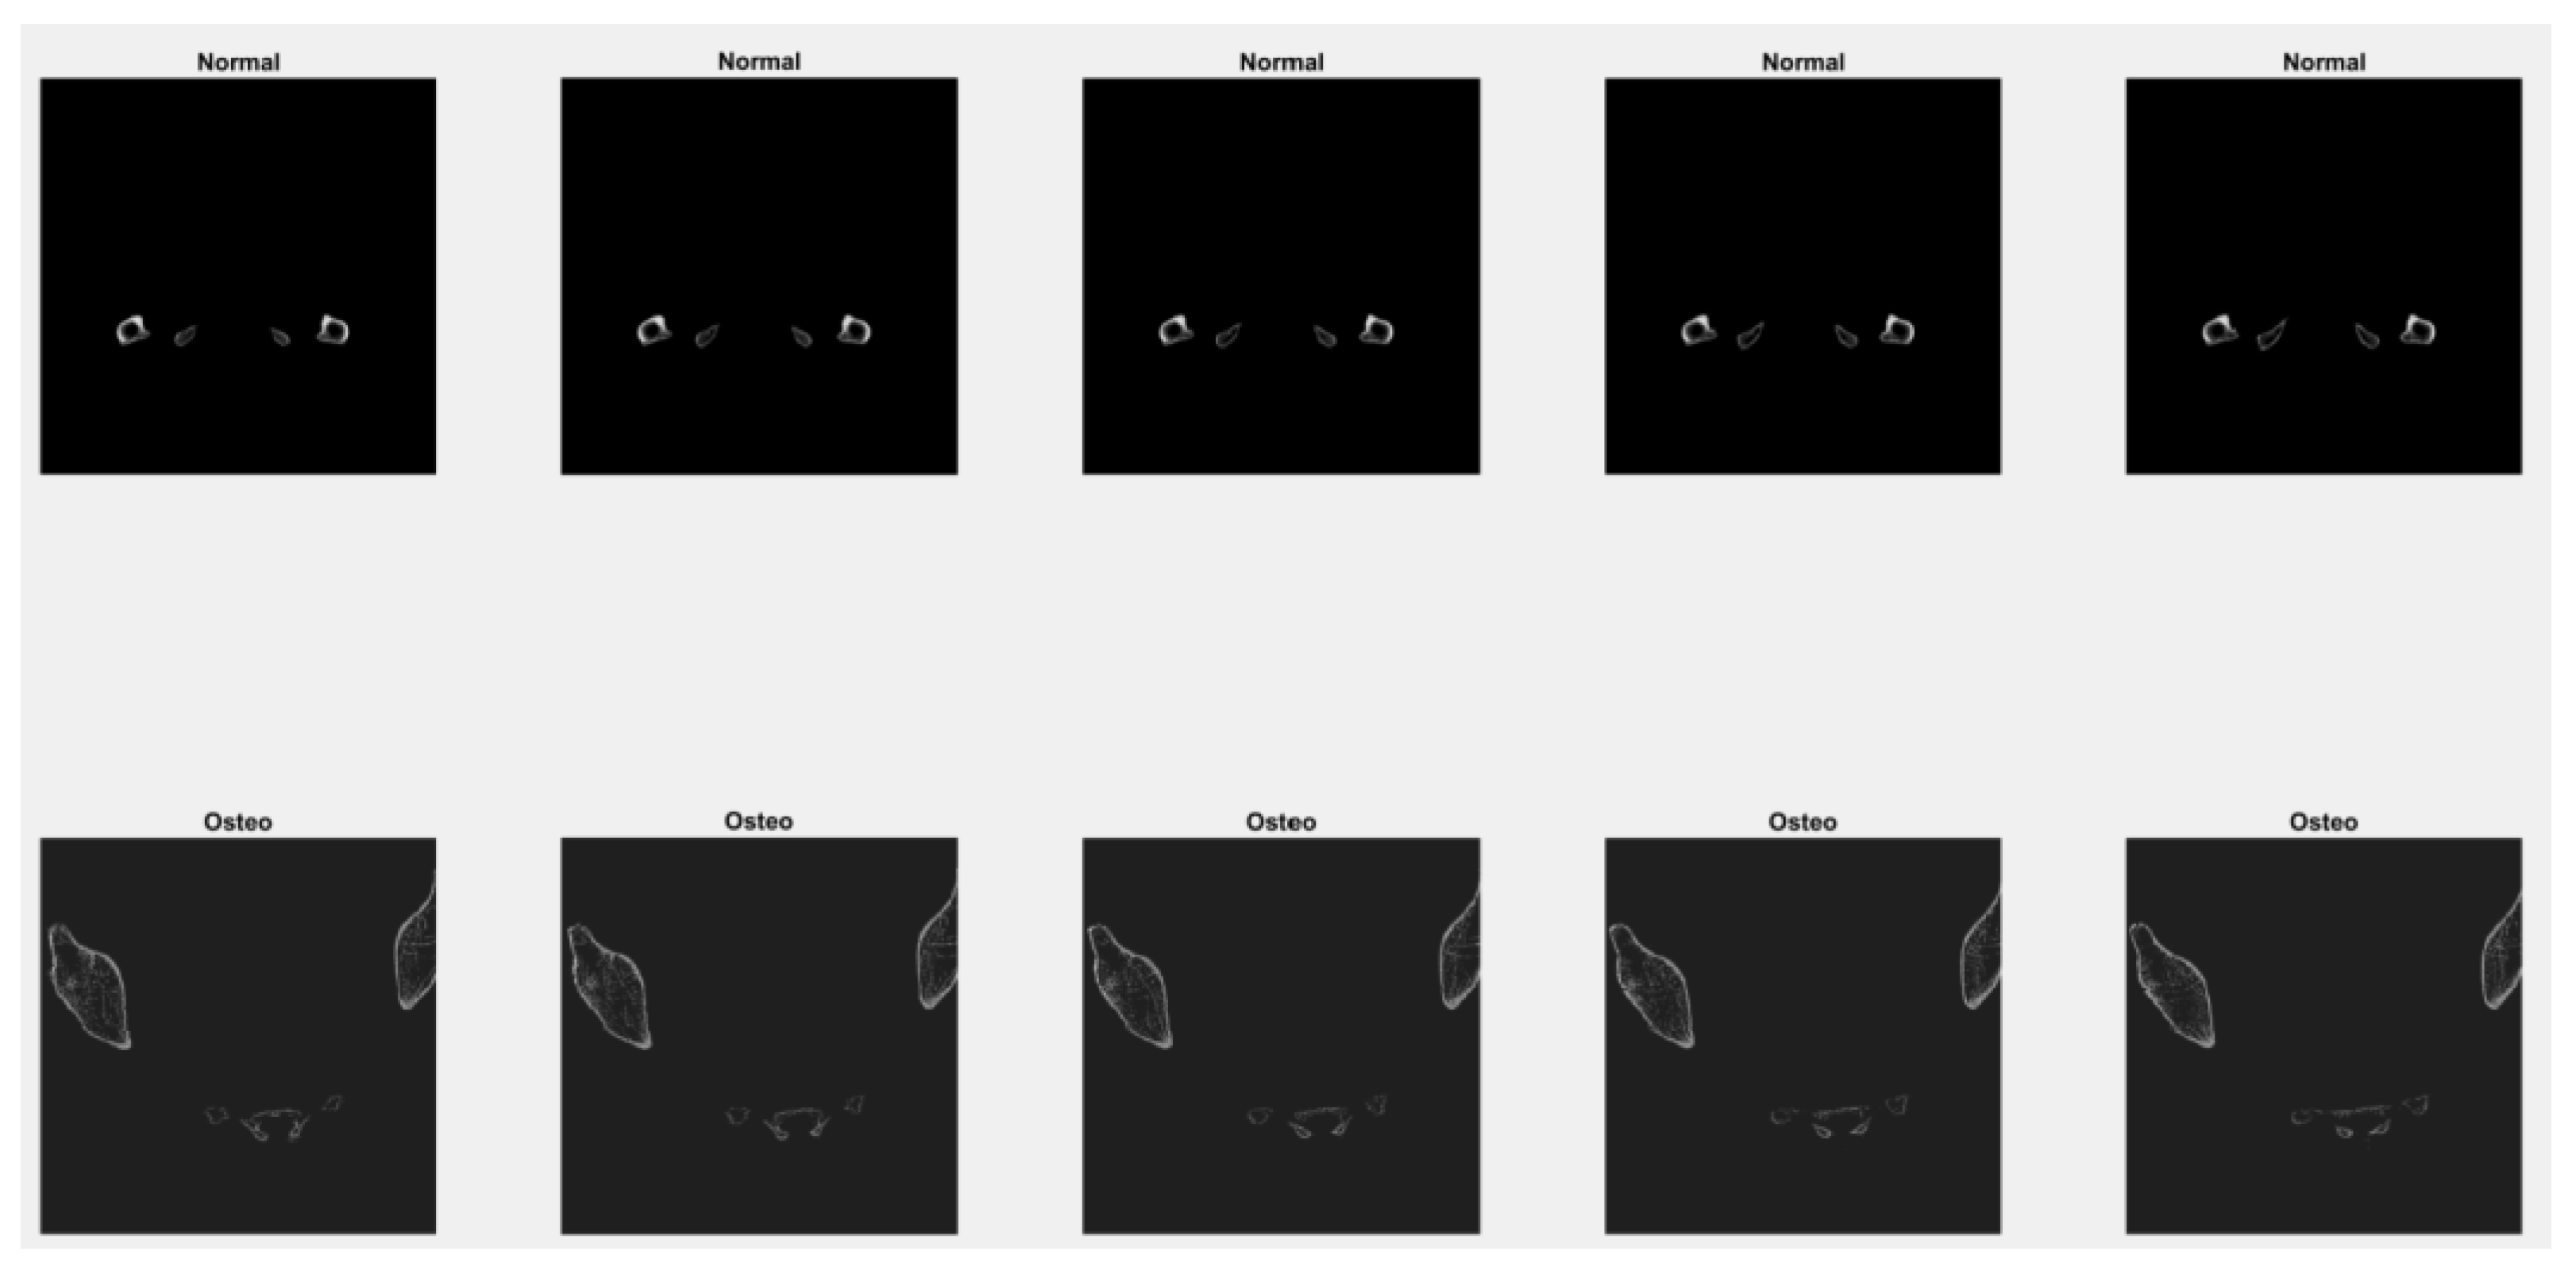

5.6. Bone Classification Using a Convolutional Neural Network: Case Study Examples

In this experiment, a deep learning model named the convolutional neural network is used to classify between normal bone and osteoporotic bone. The experiment is carried out in two scenarios; in the first scenario, the datasets used to train the models are from CT scan images of normal and osteoporotic bone only. Meanwhile, for the second scenario, the attributes of roughness index, phase index, and contrast attributes were included as the input together with the original CT scan image for both normal and osteoporotic bone. The datasets are shuffled and normalized to help better train the model. To avoid an imbalanced dataset during the training of the model, the datasets selected have the same number of normal and osteoporotic bones. The total amount of data used during the training stage is 50 images, which consist of the same number normal and osteoporosis bone images. In the testing stages, ten images consisting of five samples of normal and osteoporotic bone were used.

In the CT images used for this experiment, 3D slicing with axial slicing was selected. Examples of images taken for the training and testing stages are shown in Figure 8.

Figure 8. Samples of images for the training and testing stages of the bone classification study using CNN.